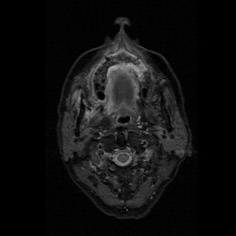

I am just getting ready to change when I see a resident running to me with case files and magnetic resonance images (MRIs) of this day’s patients. And right behind him is a patient’s relative who follows along. I go through the MRI with my ENT friend while he explains this 30-year-old patient, with cerebral abscess and both the maxillary antrum filled with gadolinium, delineating the massive involvement of complete maxillae, palate, all the paranasal sinuses, right orbit, and a cerebral abscess. I stare at the patient's relative who is now gazing at me with hope and desperation in his eyes; I am totally shaken and broken inside.

While the maxillofacial surgeons were more titled towards the contrast-enhanced CT (CECT) scans for diagnostic purposes, as we are more familiar with them, the ENT colleagues insisted on gadolinium-enhanced MRI scans of the paranasal sinuses. On routine discussion of MRIs with my ENT colleague and combining my own surgical experience with it, I observed that very often sequestration formation is a late and inconsistent finding in the palate; more often than not, there is no sequestration, yet the whole of palate was found to be dead with no architectural damage. The cause lies in the angioinvasive nature of the infection where multiple fungal thrombi block arterial supplies from various directions almost together, like guerrilla warfare against the immunologically suspended host. Hence, the only visible evidence of involvement and its extent before intervention are the MRI and surgeon’s own clinical judgement as she moves slowly towards exposure and debridement.